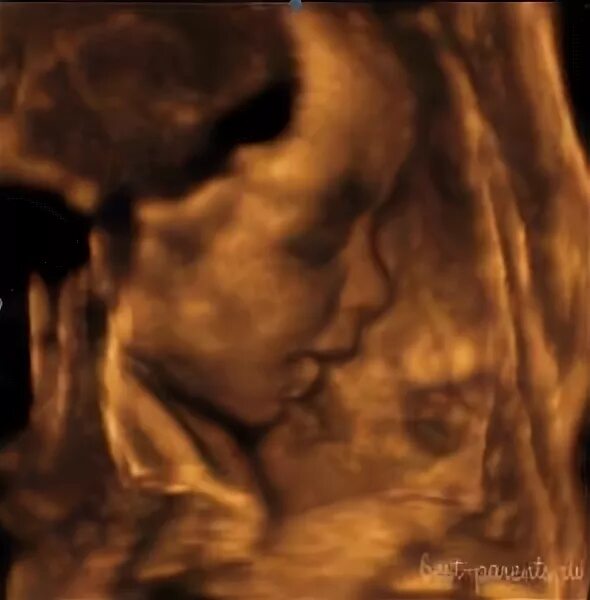

Ощущения 27 неделя